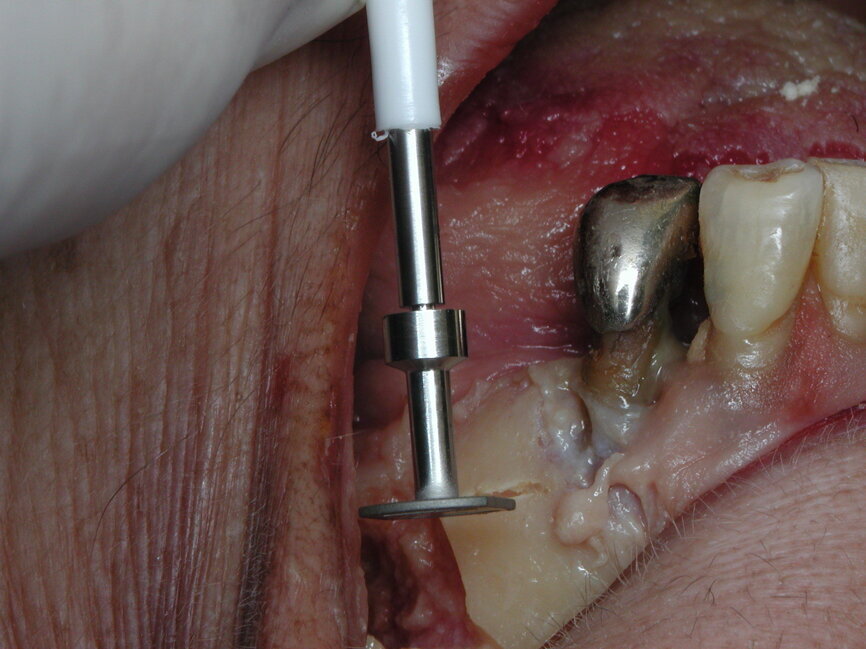

Pour cela, elle fait appel à des implants spécifiques (Diskimplant : (Fig 2a, b)) permettant un ancrage dans l’os basal de la face, non soumis à la résorption, ainsi qu’à des techniques issues de la chirurgie maxillo- faciale.

Fig. 8a : L’ostéotomie préalable à l’insertion de l’implant se réalise le plus souvent latéralement (Photo : EPSON)

Fig. 8b : L’ostéotomie préalable à l’insertion de l’implant se réalisant le plus souvent latéralement

Dans le cadre de cette nouvelle approche conceptuelle, l’étudiant va, devoir modifier sa vision traditionnelle de l’ancrage endo-osseux propre aux vis qu’il a l’habitude d’installer par voie crestale. L’ostéotomie préalable à l’insertion de l’implant se réalisant le plus souvent latéralement : (Fig 8a, b), il faudra en plus de l’évaluation des paramètres verticaux (hauteur, profondeur) tenir compte surtout des dimensions dans le sens horizontal (largeur de la crête, épaisseur des corticales osseuses). Il faudra également se familiariser avec ces implants spécialisés.